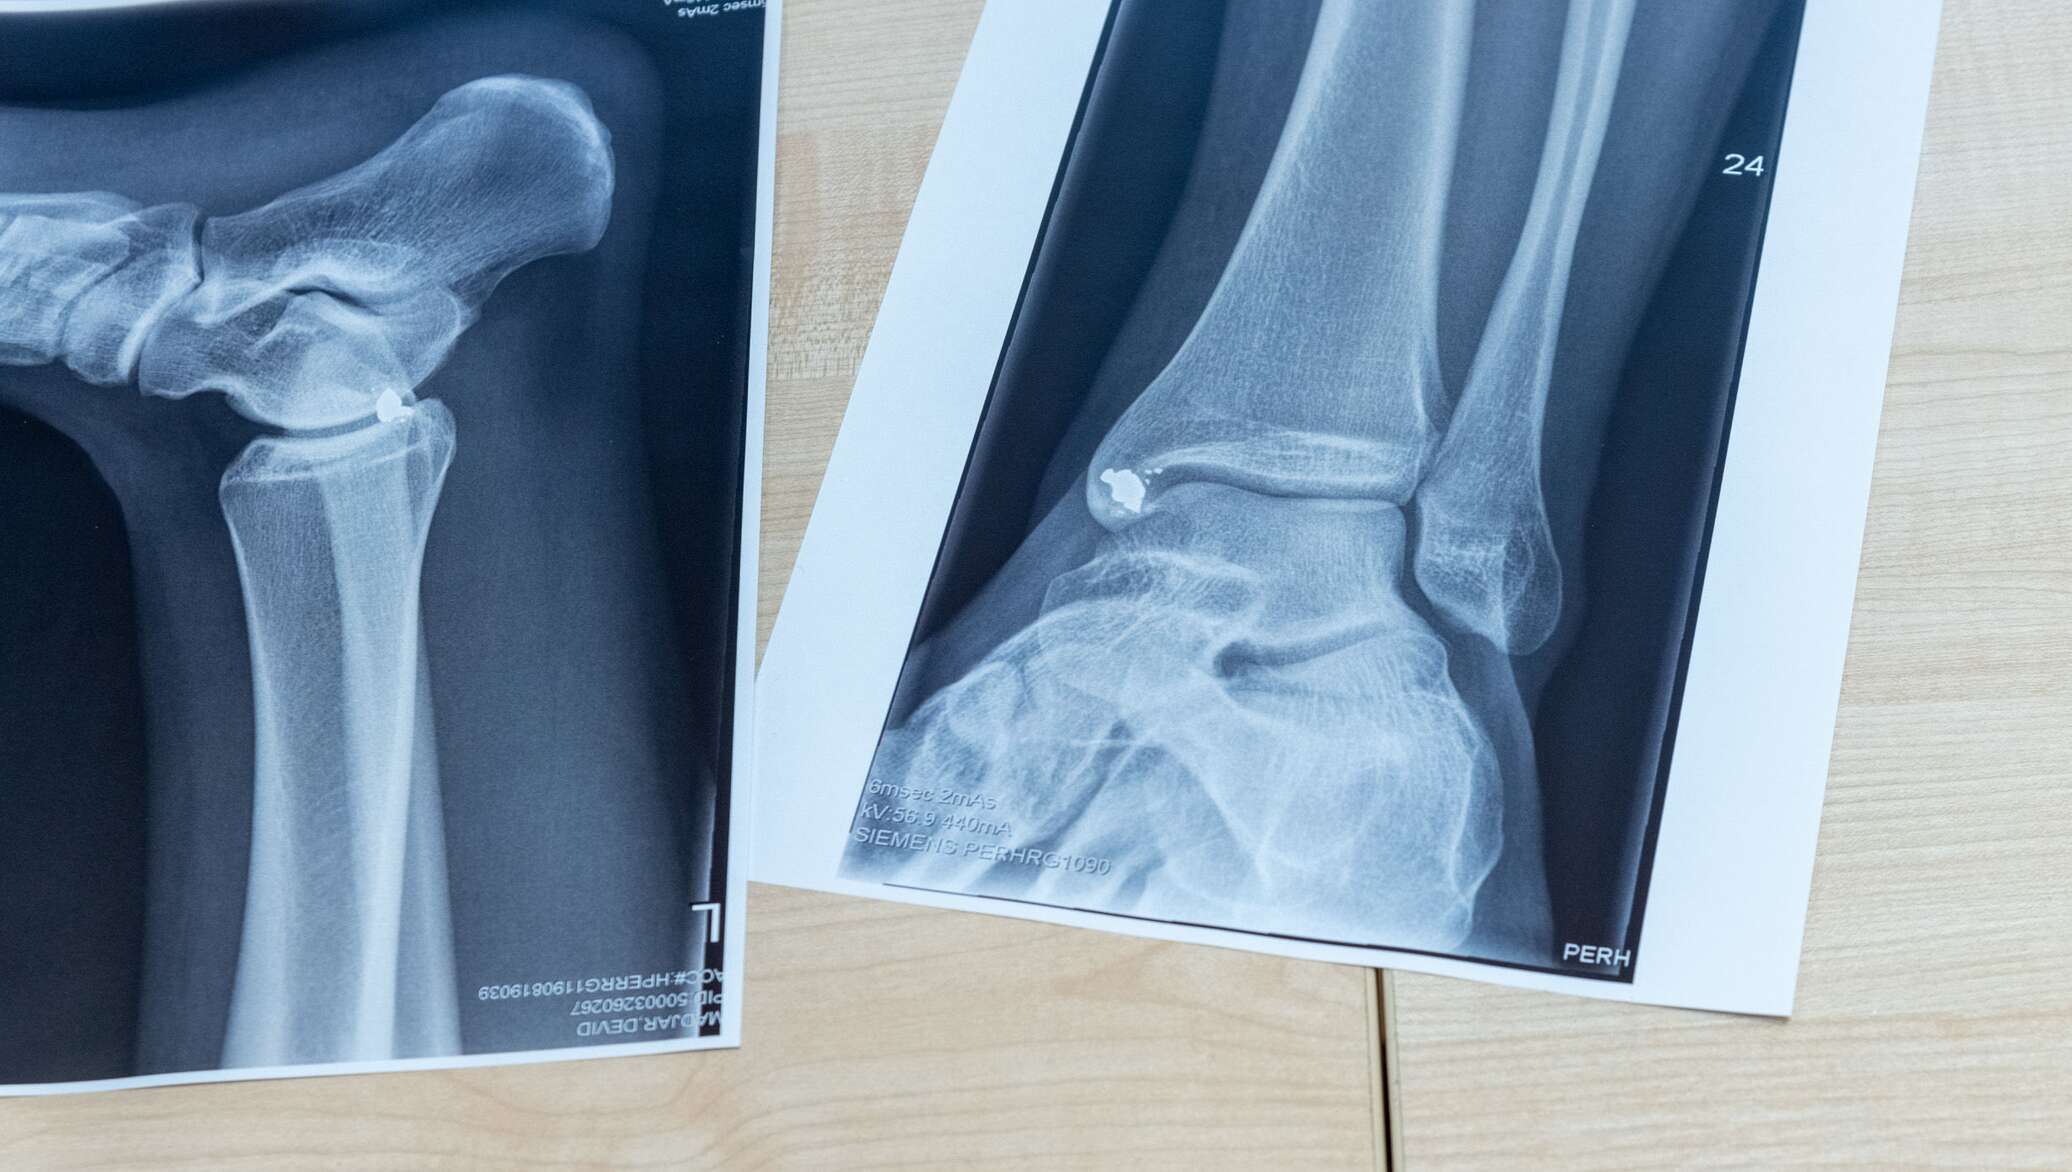

Раздел: Снимки-откровения